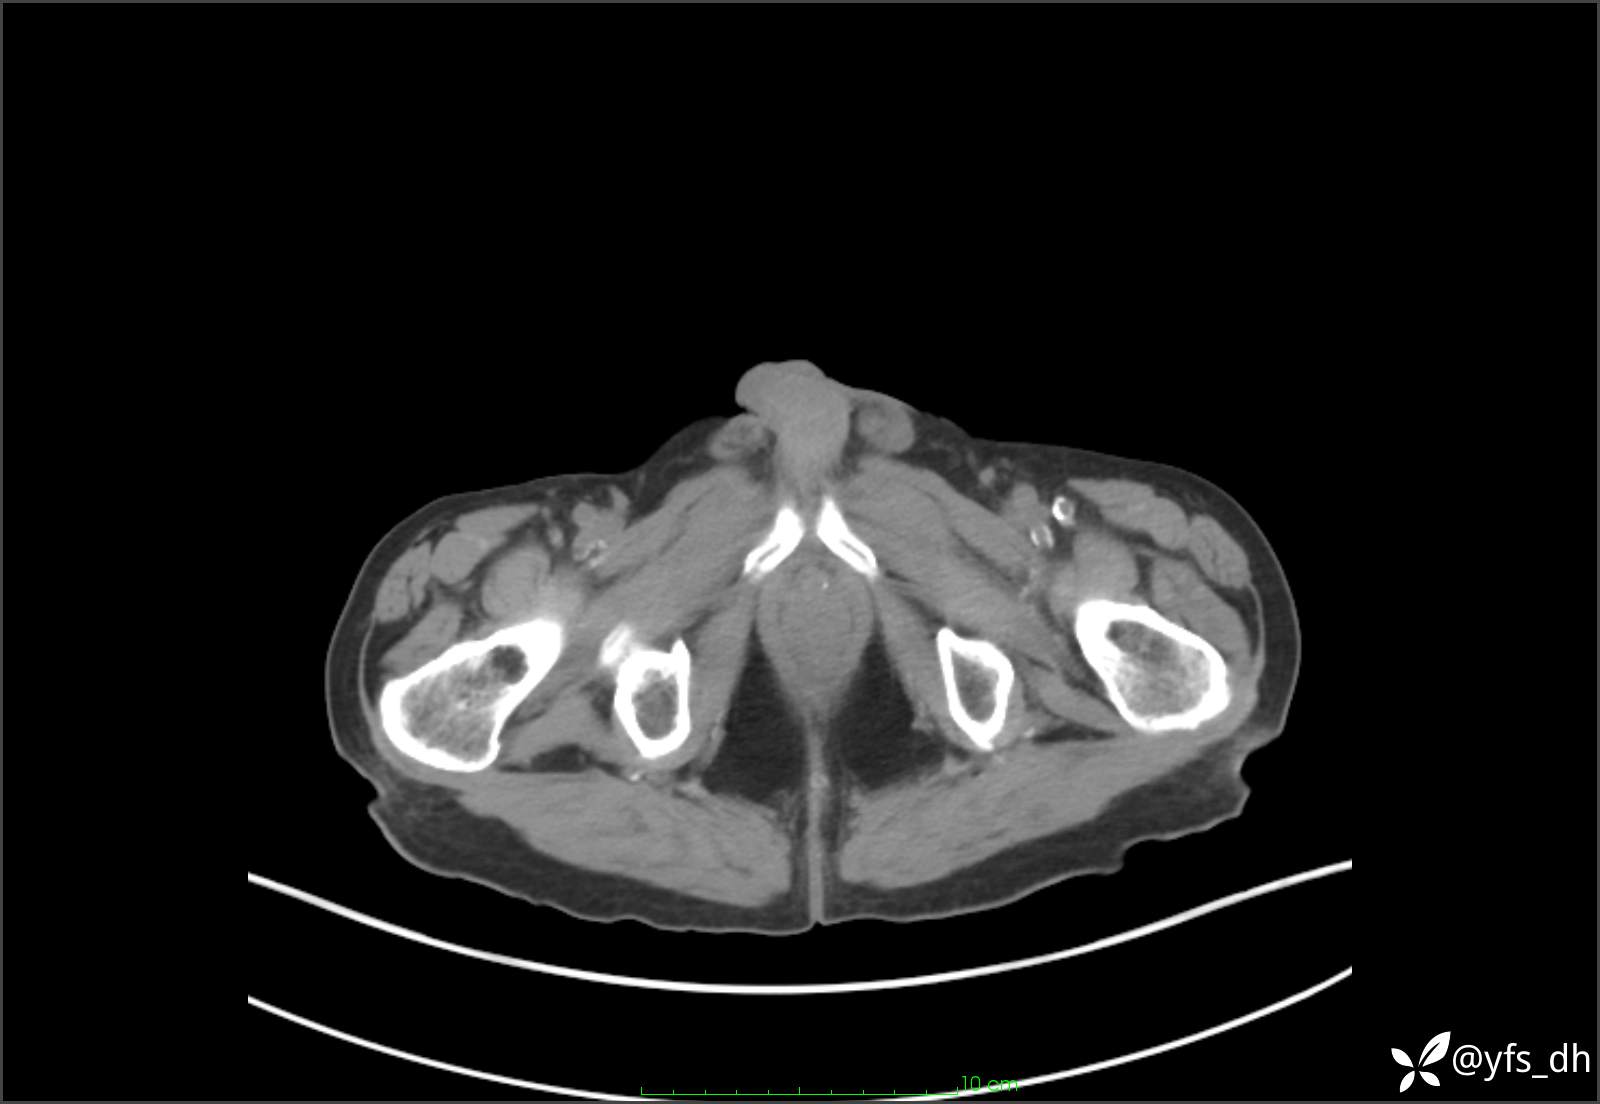

1.简要病史:患者4天前突发上腹部疼痛不适,但可以忍受。3小时前饭后突然加重,不能忍受后就诊。

2.简要手术记录:术中见腹盆腔大量肠液及粪便,乙状结肠中下段见一约3cm的破口。